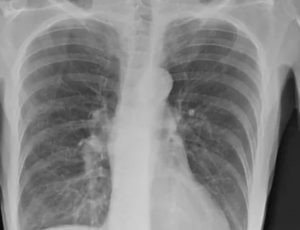

Рентген легких пациента с COVID-19 в Париже, апрель 2020 г. Reuters